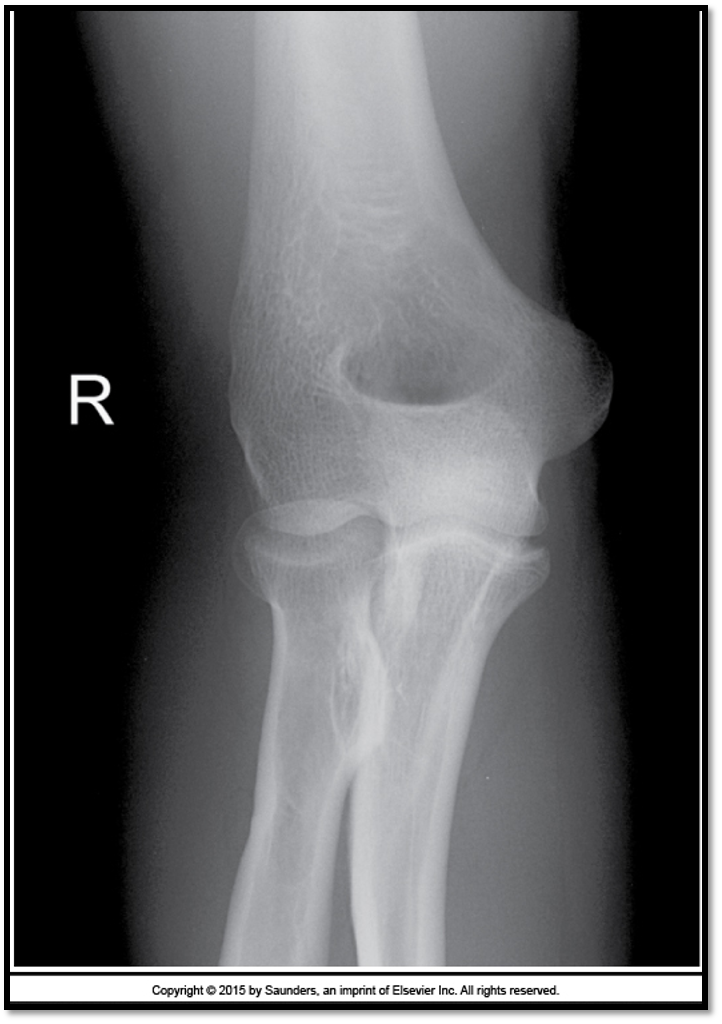

AP elbow criteria

A

Medial and lateral humeral epicondyles

are in profile

* 1/4” overlap of radial head on ulna

* 50% of the radius at the radial

tuberosity is superimposed by the ulna

* Capitulum-radial joint space is open

↳have all 3 jointson same plane

* Radius and ulna are parallel